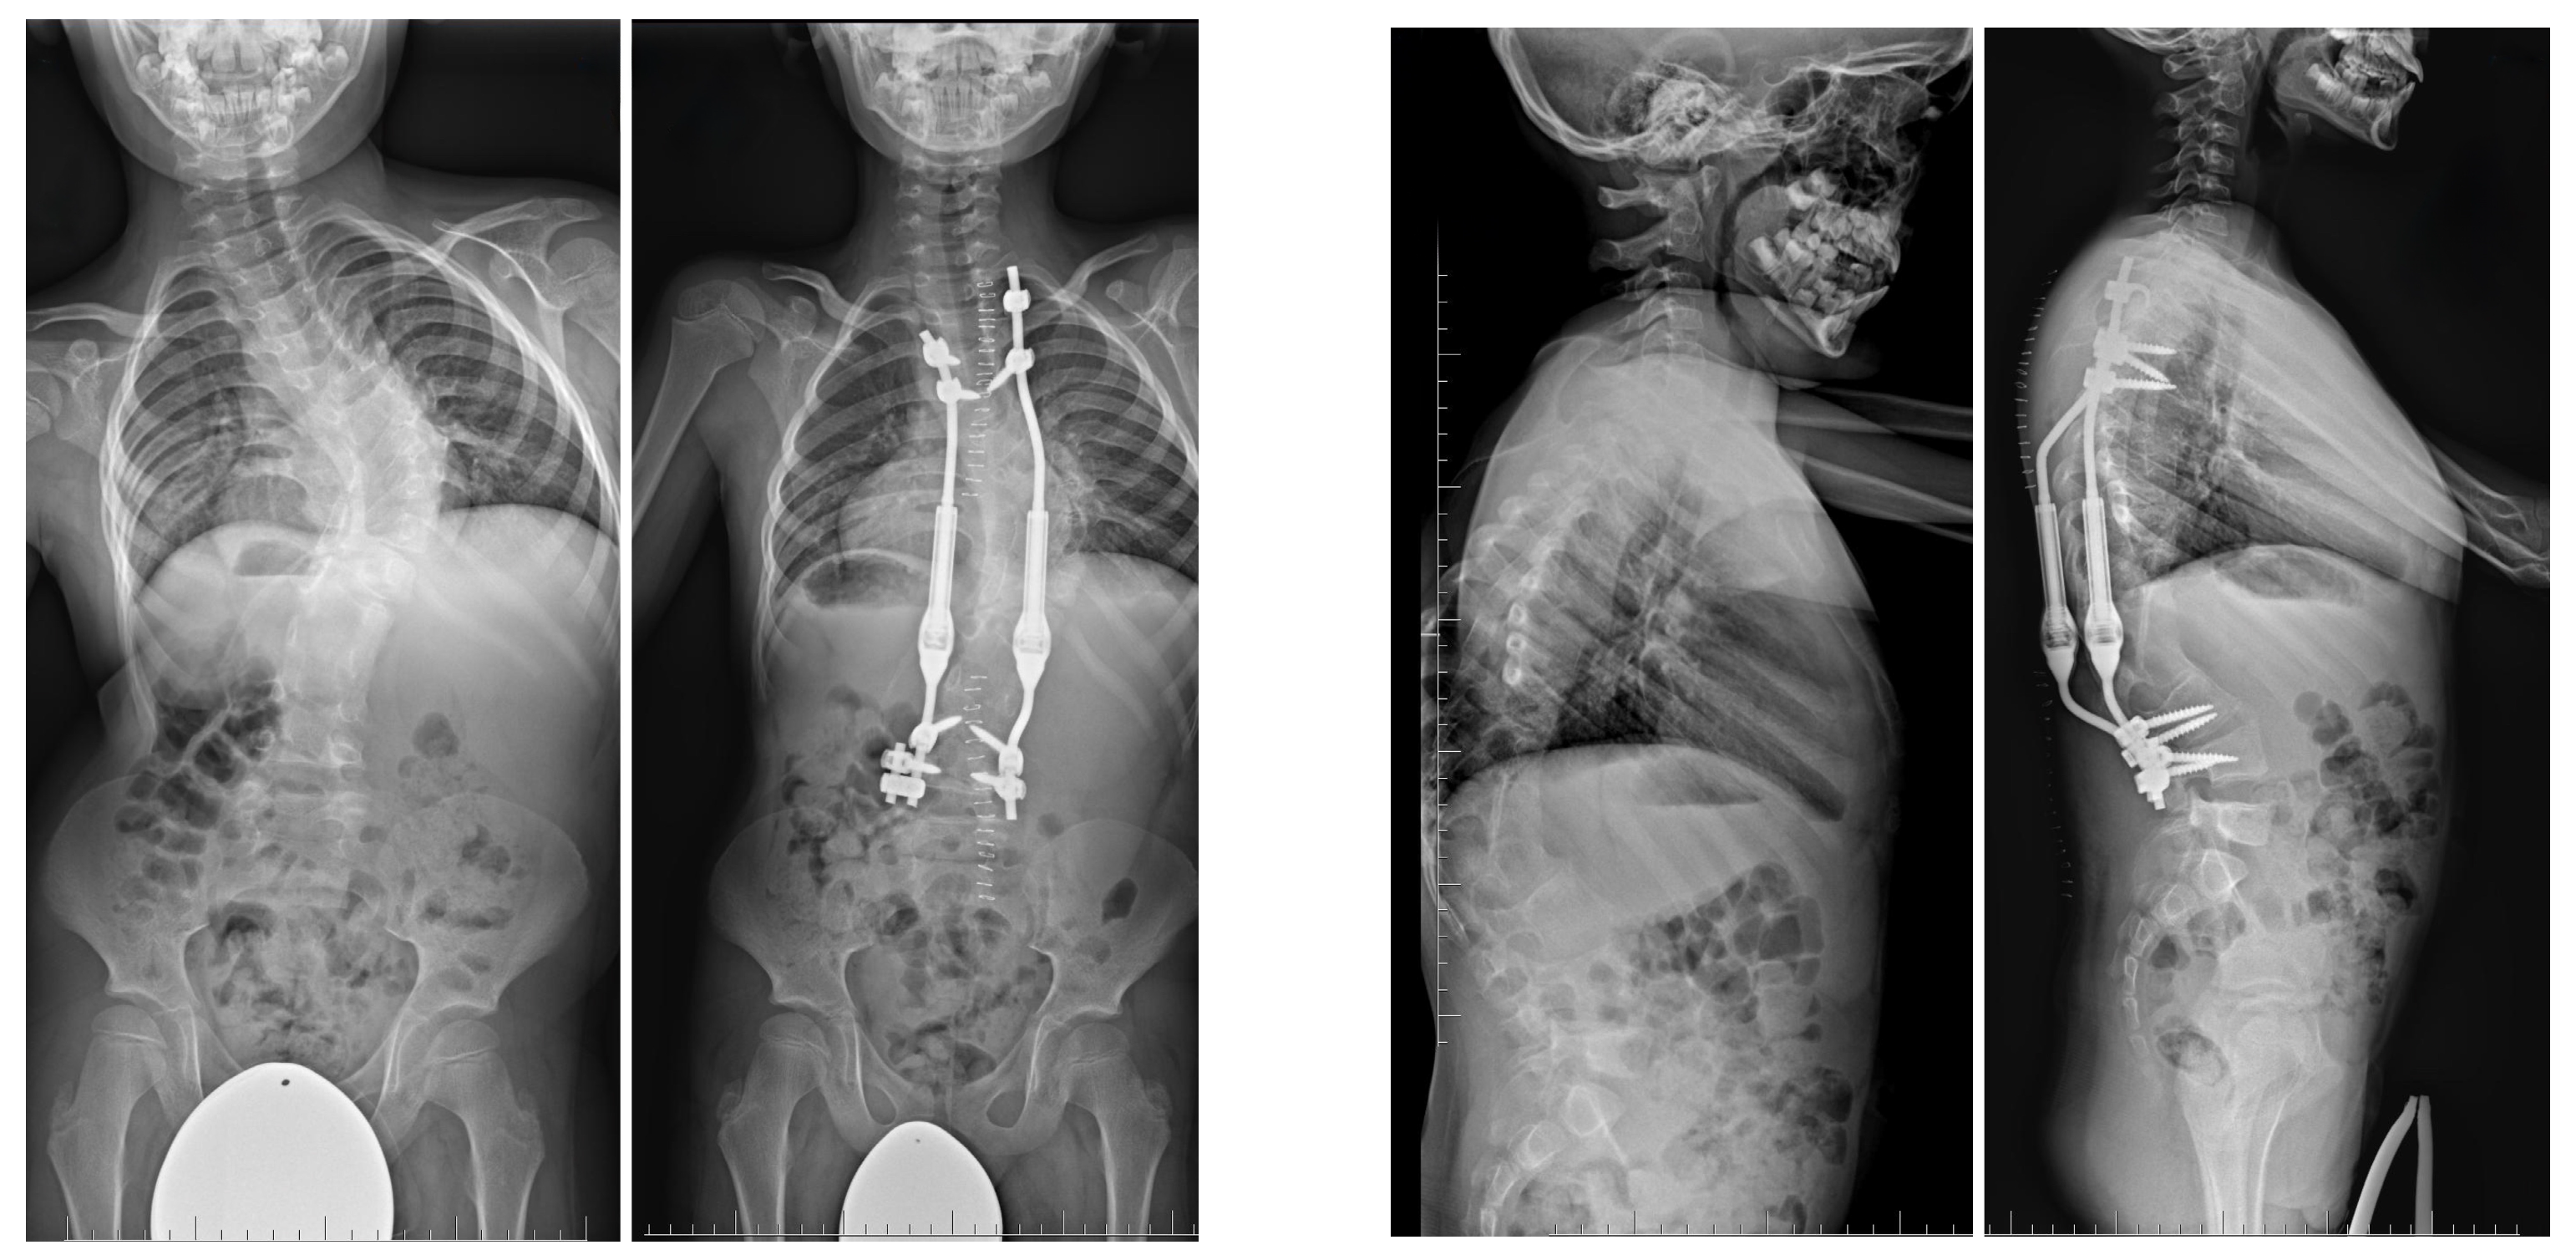

7.3.4. Growing Rod Systems

- Grabala, P.; Kowalski, P.; Rudziński, M.J.; Polis, B.; Grabala, M. The surgical management of severe scoliosis in immature patient with a very rare disease—Costello syndrome—Clinical example and brief literature review. Life 2024, 14, 740. [Google Scholar] [CrossRef]

- Grabala, P.; Gupta, M.C.; Pereira, D.E.; Latalski, M.; Danielewicz, A.; Glowka, P.; Grabala, M. Radiological outcomes of magnetically controlled growing rods for the treatment of children with various etiologies of early-onset scoliosis: A multicenter study. J. Clin. Med. 2024, 13, 1529. [Google Scholar] [CrossRef]

- Grabala, P.; Helenius, I.J.; Chamberlin, K.; Galgano, M. Less-invasive approach to early-onset scoliosis: Surgical technique for magnetically controlled growing rod (MCGR) based on treatment of 2-year-old child with severe scoliosis. Children 2023, 10, 555. [Google Scholar] [CrossRef]